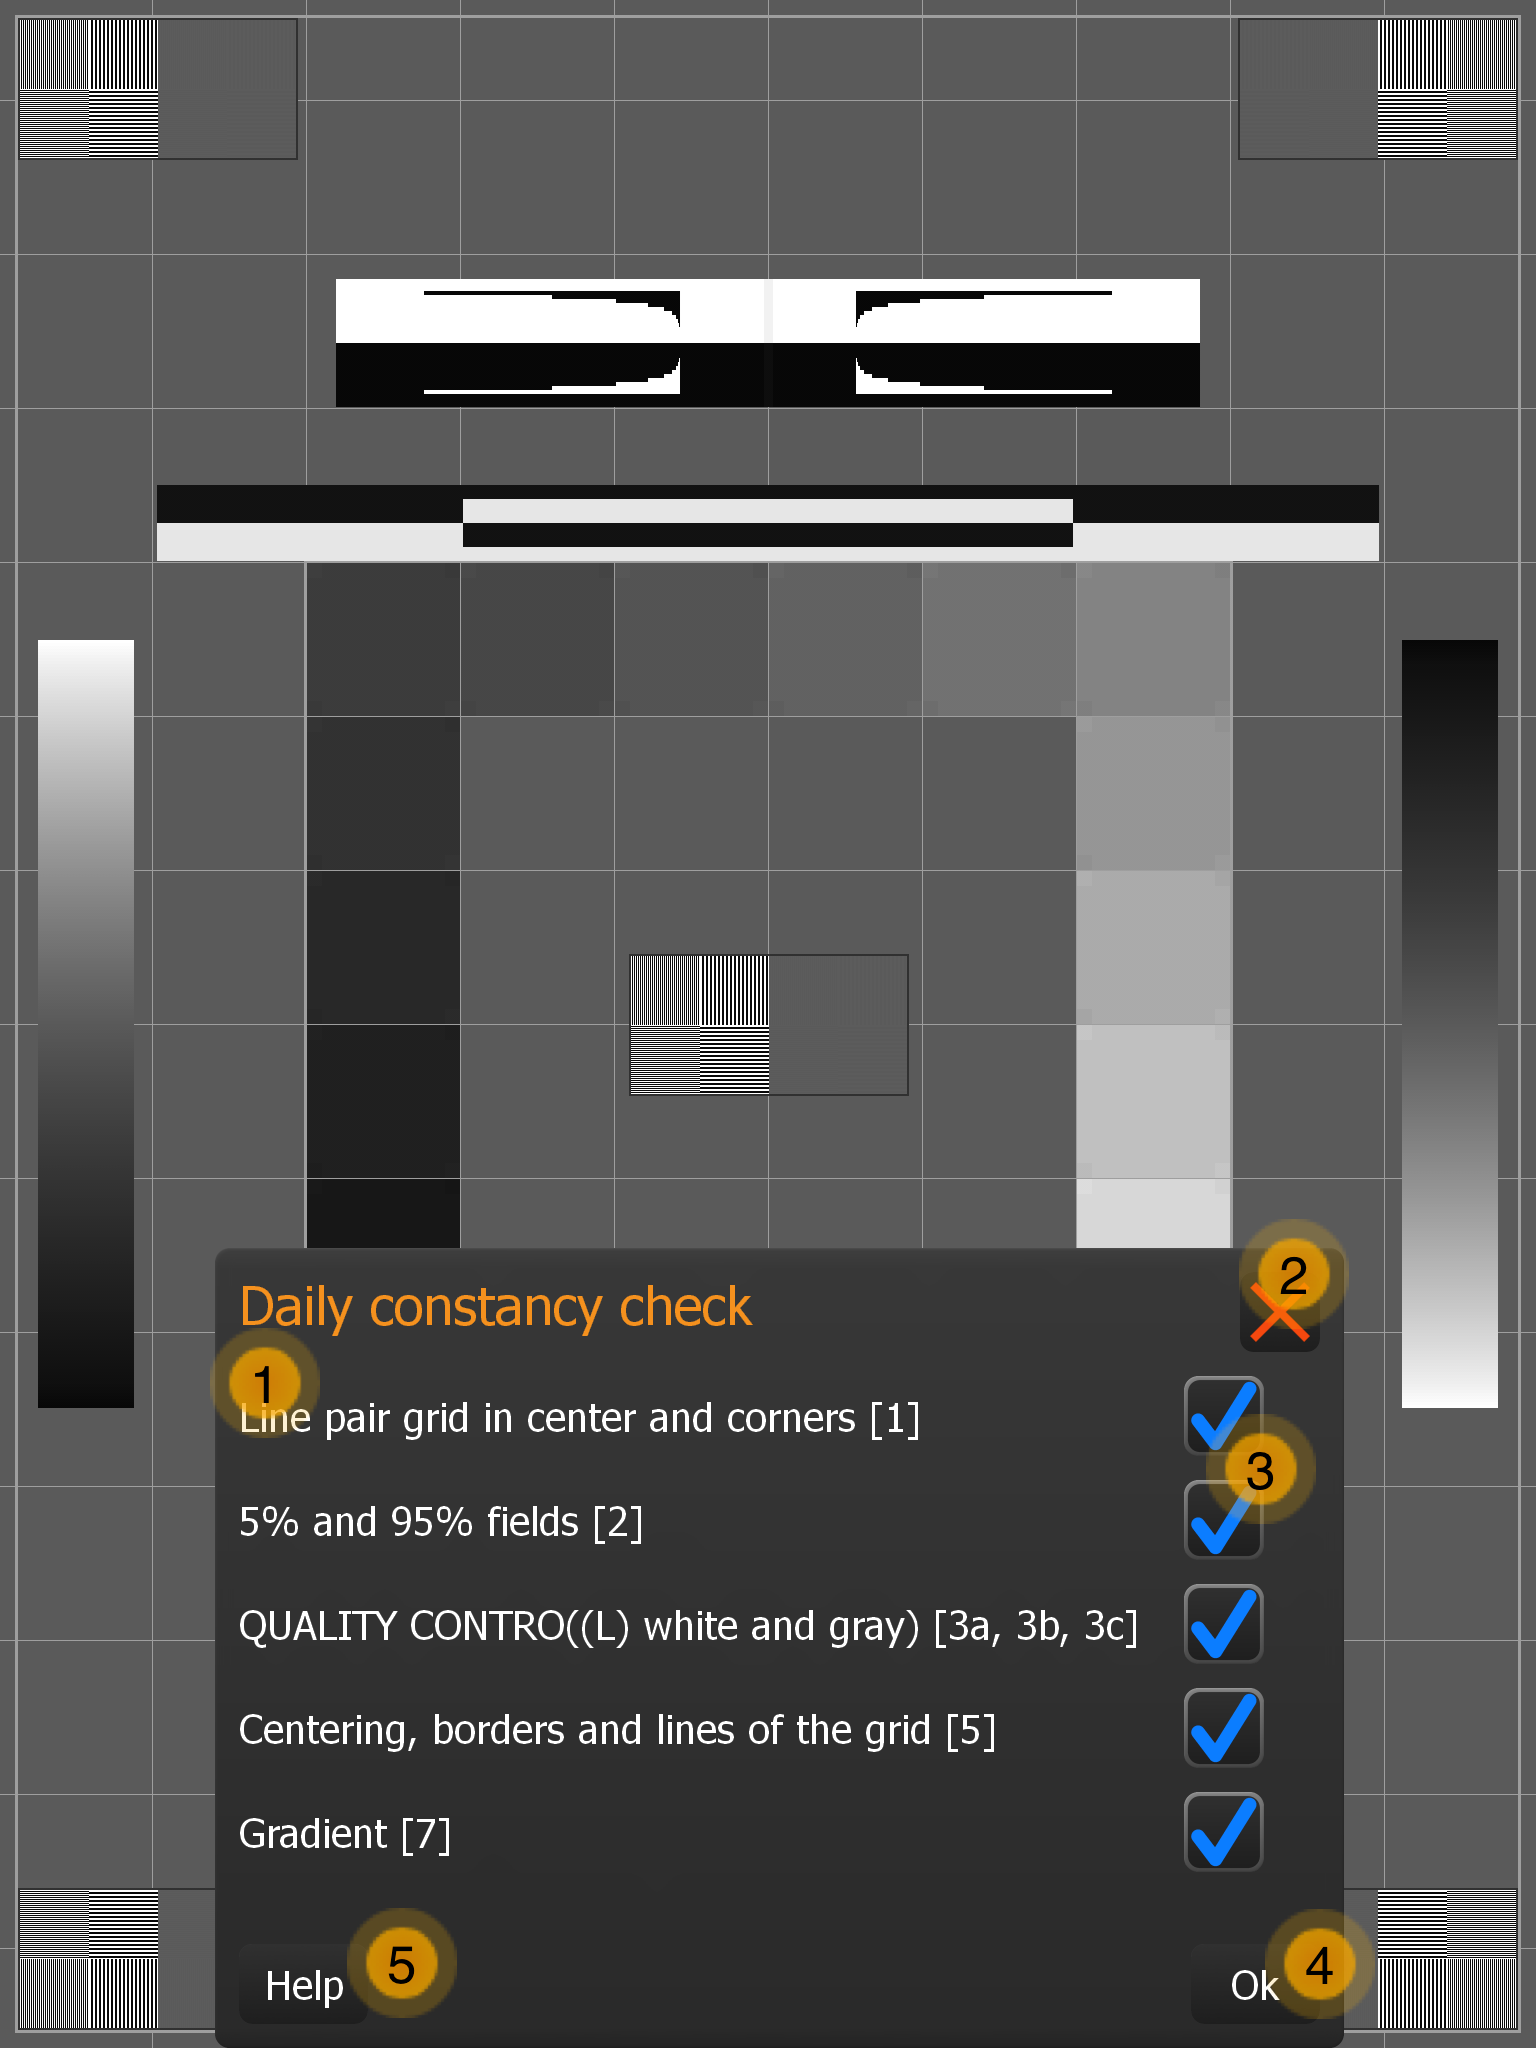

9.9. Konstanzprüfung

-

Prüfkriterien (Die Zahlen beziehen sich auf die Testbildelemente aus der DIN 6868-157).

-

Blenden Sie die Formularmaske aus. Diese kann jederzeit wieder aufgerufen werden (Tap auf das Testbild blendet Button mit Haken ein).

-

Markieren Sie das Kriterium mit dem Haken, falls die Bedingung erfüllt ist.

-

Speichern Sie die Durchführung und deren Ergebnisse ab.

-

Erhalten Sie mehr Informationen (öffnet das Handbuch, siehe nachfolgender Abschnitt).

Die Abbildung zeigt die einzelnen Testbildelemente. Folgende Punkte sind im Detail zu prüfen (nach Norm):

-

Sichtbarkeit der Linienpaar-Raster mit hohem KONTRAST in der Mitte und in den vier Ecken des TESTBILDES(Testbildelement 1)?

-

Sichtbarkeit der 5 %- und 95 %-Felder (Testbildelement 2)?

-

Qualitätskontrolle:

-

Im weißen und grauen Feld: „QUALITY CONTROL“ für alle Raumklassen

-

Im schwarzen Feld:

-

Mammographie:"QUALITY CONTROL".

-

RK1 (? 50 lx):"QUALITY CONTRO".

-

RK2 (? 100 lx):"QUALITY CONT".

-

RK3 (? 500 lx):"QUALITY CON" (test pattern element 3)?

-

-

-

Sichtbarkeit der Grenzen und Linien des Rasters und der Zentrierung des Rasters im aktiven Bereich des BILDWIEDERGABEGERÄTES(Testbildelement 5)?

-

Kontinuität des Erscheinungsbildes der Verlaufsbalken (Testbildelement 7)?